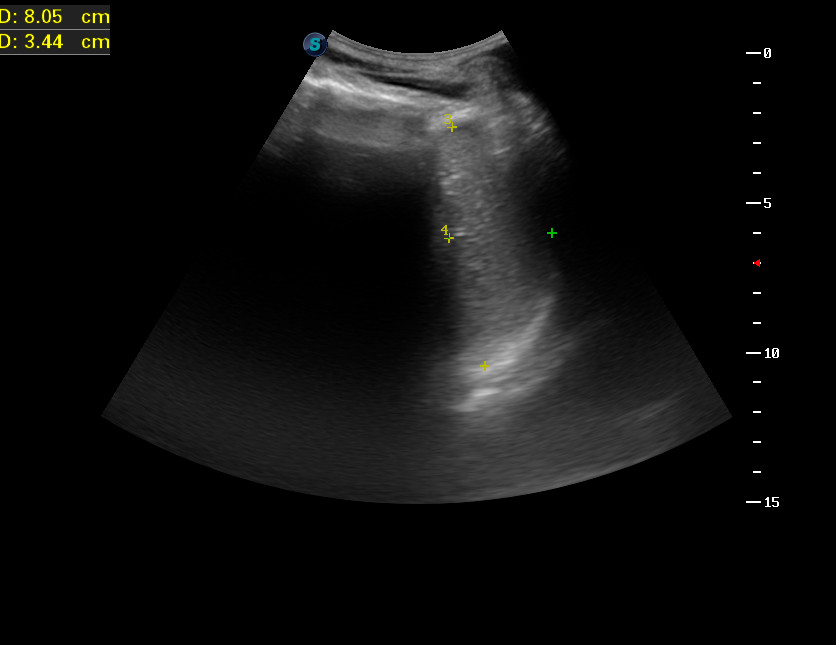

Исследование 2014 года.

Женщина 65 лет, с мерцательной аритмией и сердечной недостаточностью.

Вот такая селезенка.

333_20140320_ABDOMEN_0007.jpg